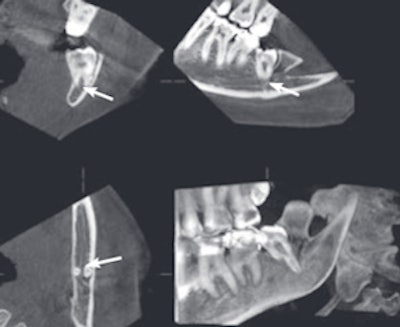

An example of cone-beam CT. In this instance, the lower left third molar (d. 38) was imaged after panoramic radiograph with CBCT. The arrows mark the mandibular canal. Images courtesy of Dr. Anni Suomalainen.

CBCT is a radiographic imaging method that allows accurate 3D imaging of hard tissues. During a CBCT scan, the scanner rotates around the patient's head (180° to 360°), obtaining multiple sequential planar projection images by a 2D detector. The scanning software collects the data, which are then processed to create a volumetric dataset with isotopic voxels with varying field-of-view.

The pitfalls with CBCT are artifacts, which are either physics-based, patient-related, or cone-beam-related. For example, metal objects in the scan field can cause severe streaking artifacts, and patient motion during the exposure can lead to lack of sharpness in reconstructed images.